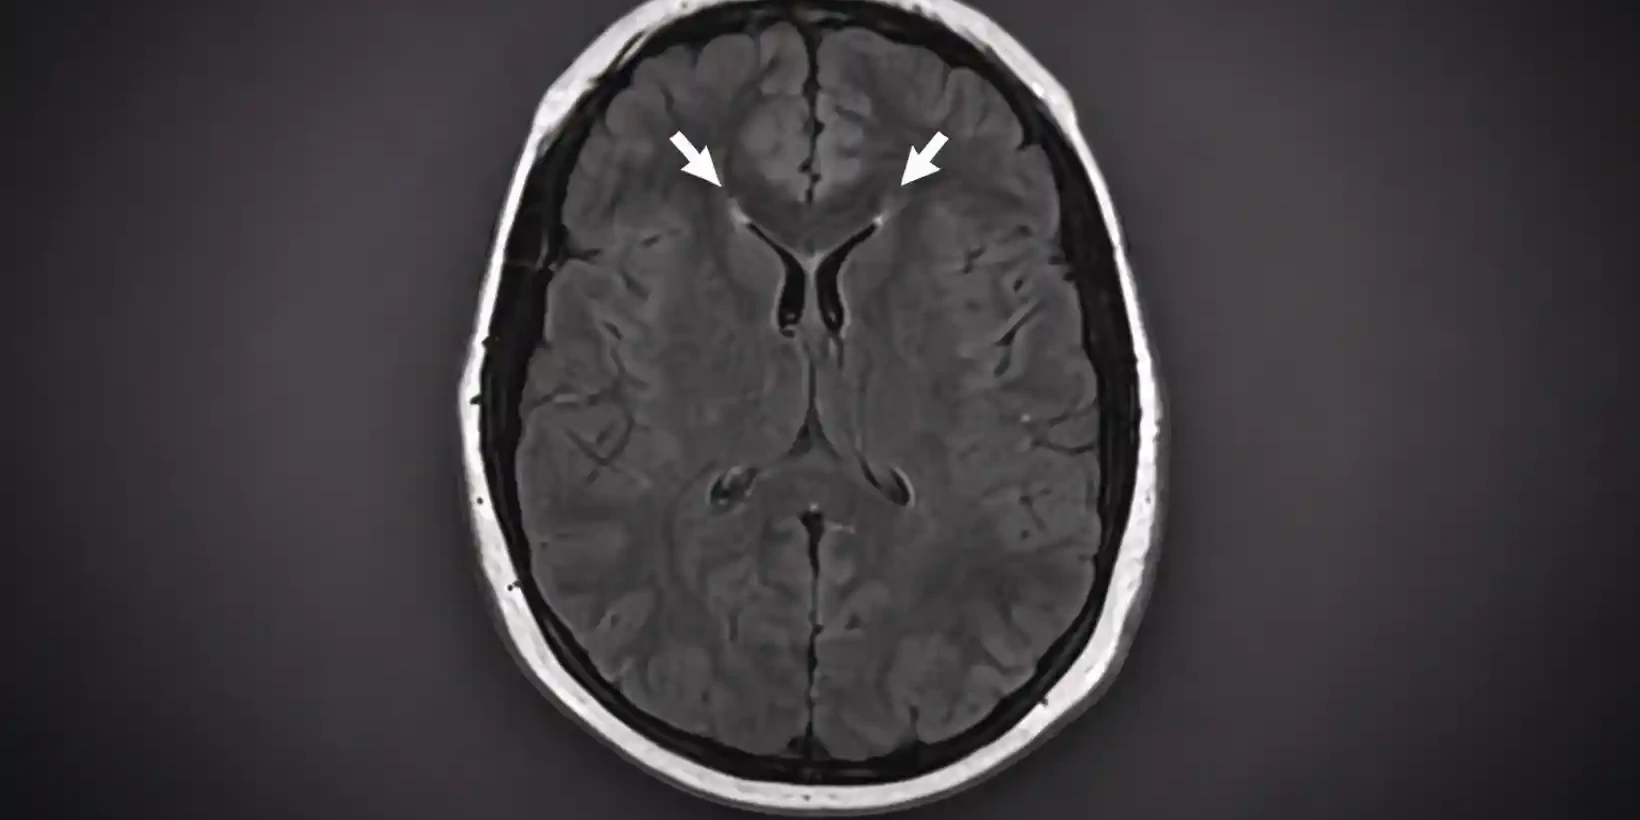

Cerebral Edema: Causes, Types, Symptoms & Treatment Explained

Edema means fluid builds up in a part of the body where it should not be. When this buildup happens…